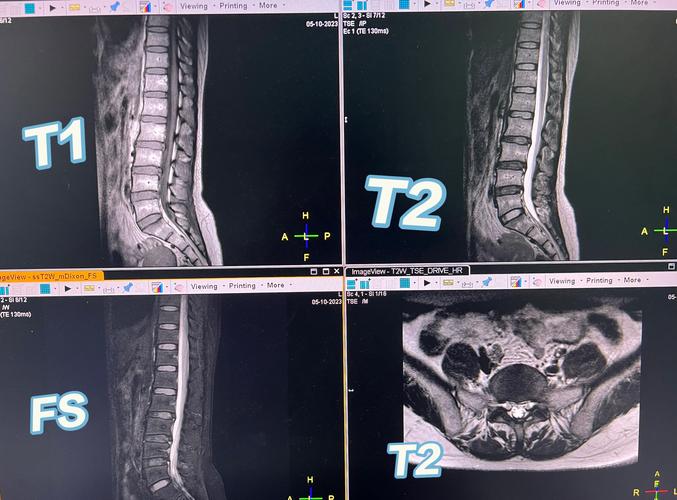

在我們聊生理期跟MRI的關係之前,先來簡單認識一下MRI是什麼吧!MRI,全名為磁振造影,它是一種非常先進的醫學影像檢查技術。它不像X光或電腦斷層(CT)那樣使用游離輻射,而是利用強大的磁場和無線電波來偵測人體組織中的水分子,然後透過電腦轉換成精細的影像。

由於MRI能夠提供非常清晰的軟組織影像,對於大腦、脊椎、關節、腹部器官,甚至是骨盆腔的許多病變,都有著極佳的診斷能力。它能看到許多X光或超音波看不到的細節,這也是為什麼醫師會推薦進行MRI檢查的原因。

針對這個疑慮,我們需要分情況討論。對於大多數非骨盆腔的MRI檢查(例如腦部、脊椎、關節、腹部器官如肝膽腎等),生理期對影像的準確性是幾乎沒有影響的。因為這些部位的成像原理和病變特徵,與女性的月經週期沒有直接的生理連結。

然而,若檢查部位是女性的骨盆腔,情況就會稍微有點「微妙」了。由於子宮、卵巢等生殖器官受到荷爾蒙的周期性影響,子宮內膜的厚度、血流灌注、甚至卵巢濾泡的發育狀況,在月經週期的不同階段確實會有變化。例如,子宮內膜在月經來潮時會剝落,在月經結束後會開始增生。這些正常生理上的改變,放射科醫師在判讀時都會納入考量。

通常來說,這些變化並不會影響到大多數病灶(如子宮肌瘤、子宮腺肌症、卵巢囊腫)的診斷。但如果醫師特別需要評估子宮內膜的細微病變(如內膜息肉、內膜增生或子宮腔內的沾黏),那麼月經期間的經血可能會稍微遮蔽或影響判讀。在這種情況下,醫師可能會建議在月經剛結束、子宮內膜較薄且經血已清除乾淨的「月經週期初期」(例如月經的第7-14天)進行檢查,以獲得最清晰的內膜影像。但這並非絕對,最終還是要看妳的醫師根據檢查目的來決定最佳時機。